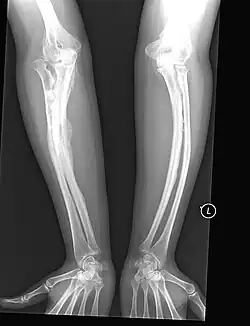

The most direct example of the role of Sp7 in human disease has been in recessive osteogenesis imperfecta (OI), which is a type-I collagen related disease that causes a heterogeneous set of bone-related symptoms which can range from mild to very severe. Generally this disease is caused by mutations in Col1a1 or Col1a2 which are regulators of collagen growth. OI-causing mutations in these collagen genes are generally heritable in an autosomal-dominant fashion. However, there has been a recent case of a patient with recessive OI with a documented frameshift mutation in Sp7/Osx as the etiological origin of the disease.[11] This patient displayed abnormal fracturing of the bones after relatively minor injuries and markedly delayed motor milestones, requiring assistance to stand at age 6 and was unable to walk at age 8 due to pronounced bowing of the arms and legs. This provides a direct link between the Sp7 gene and the OI disease phenotype.

Bowed bones of the arms as seen in an adult osteogenesis imperfecta patient.